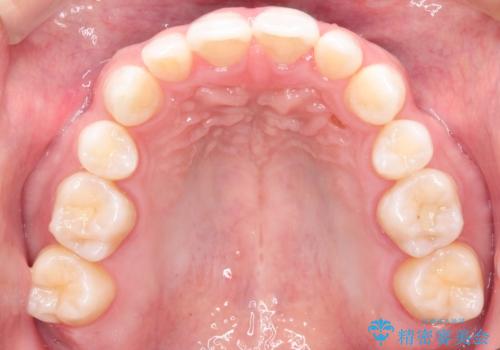

【インビザライン】笑った時の歯並びを綺麗にしたい

- 笑った時の歯の見え方を綺麗にしたいことを主訴に来院されました。

インビザラインにて治療を行なっております。

シミュレーションを用いてることで患者さんと最終的なゴールを確認し行いながら治療を行うことができます。